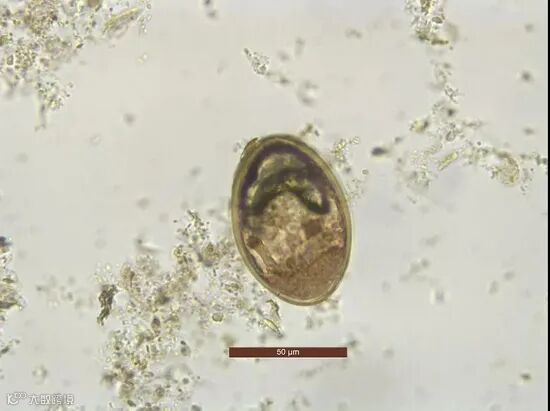

据了解,项目共分析了秦人墓地259座墓葬的腹土样品(包括1座东汉墓),在其中28座秦人墓中发现人体寄生虫遗存,包括似蚓蛔线虫卵(Ascaris lumbricoides)、异形吸虫科吸虫卵(Heterophyids spp。)、粪类圆线虫卵(Strongyloides stercoralis)。

研究人员发现,秦人墓腹土样品中,有20份样品发现蛔虫卵,总体感染率为7.75%。而人群之间虽然存在不同分区、不同葬式、不同葬具随葬品,但蛔虫感染率只是稍有不同,达不到统计学上的显著性差异。这说明,从战国晚期到西汉中期,在这里生活的各类人群受到蛔虫病的威胁程度是相似的,他们的社会等级和财富等级所对应的生活方式、居住环境可能差异不大,反映了社会结构可能比较简单。

大唐电厂M47人骨腹土蛔虫卵